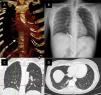

(A) Reconstruction of thoracic CT. Anomalous systemic artery arising from the abdominal aorta (white arrow). (B) 3-Month-follow-up with chest X-ray show the coils in the anomalous artery in the RLL. (C and D) Anomalous systemic artery arising from the abdominal aorta supplying a normal lung parenchyma.

The first episode happened one year prior with limited symptoms after conservative treatment in another institution. Chest X-ray, blood and functional lung tests were unremarkable. Eventually, a thoracic computed tomography (CT) angiography showed an anomalous systemic artery arising from the abdominal aorta (Fig. 1A). The artery irrigated the posterior-basal segment of right lower lobe (RLL) with no other alterations in pulmonary parenchyma. Pulmonary and cardiac shunts were ruled out.

Soon after the procedure, the patient presented fever and pleuritic pain due to a mild right pleural effusion and a small area of pulmonary infarct, managed with conventional analgesia. A 3-month-follow-up CT-angiography (Fig. 1B and C) showed the coils in the anomalous occluded artery with no other remarkable findings. The patient currently remains asymptomatic.